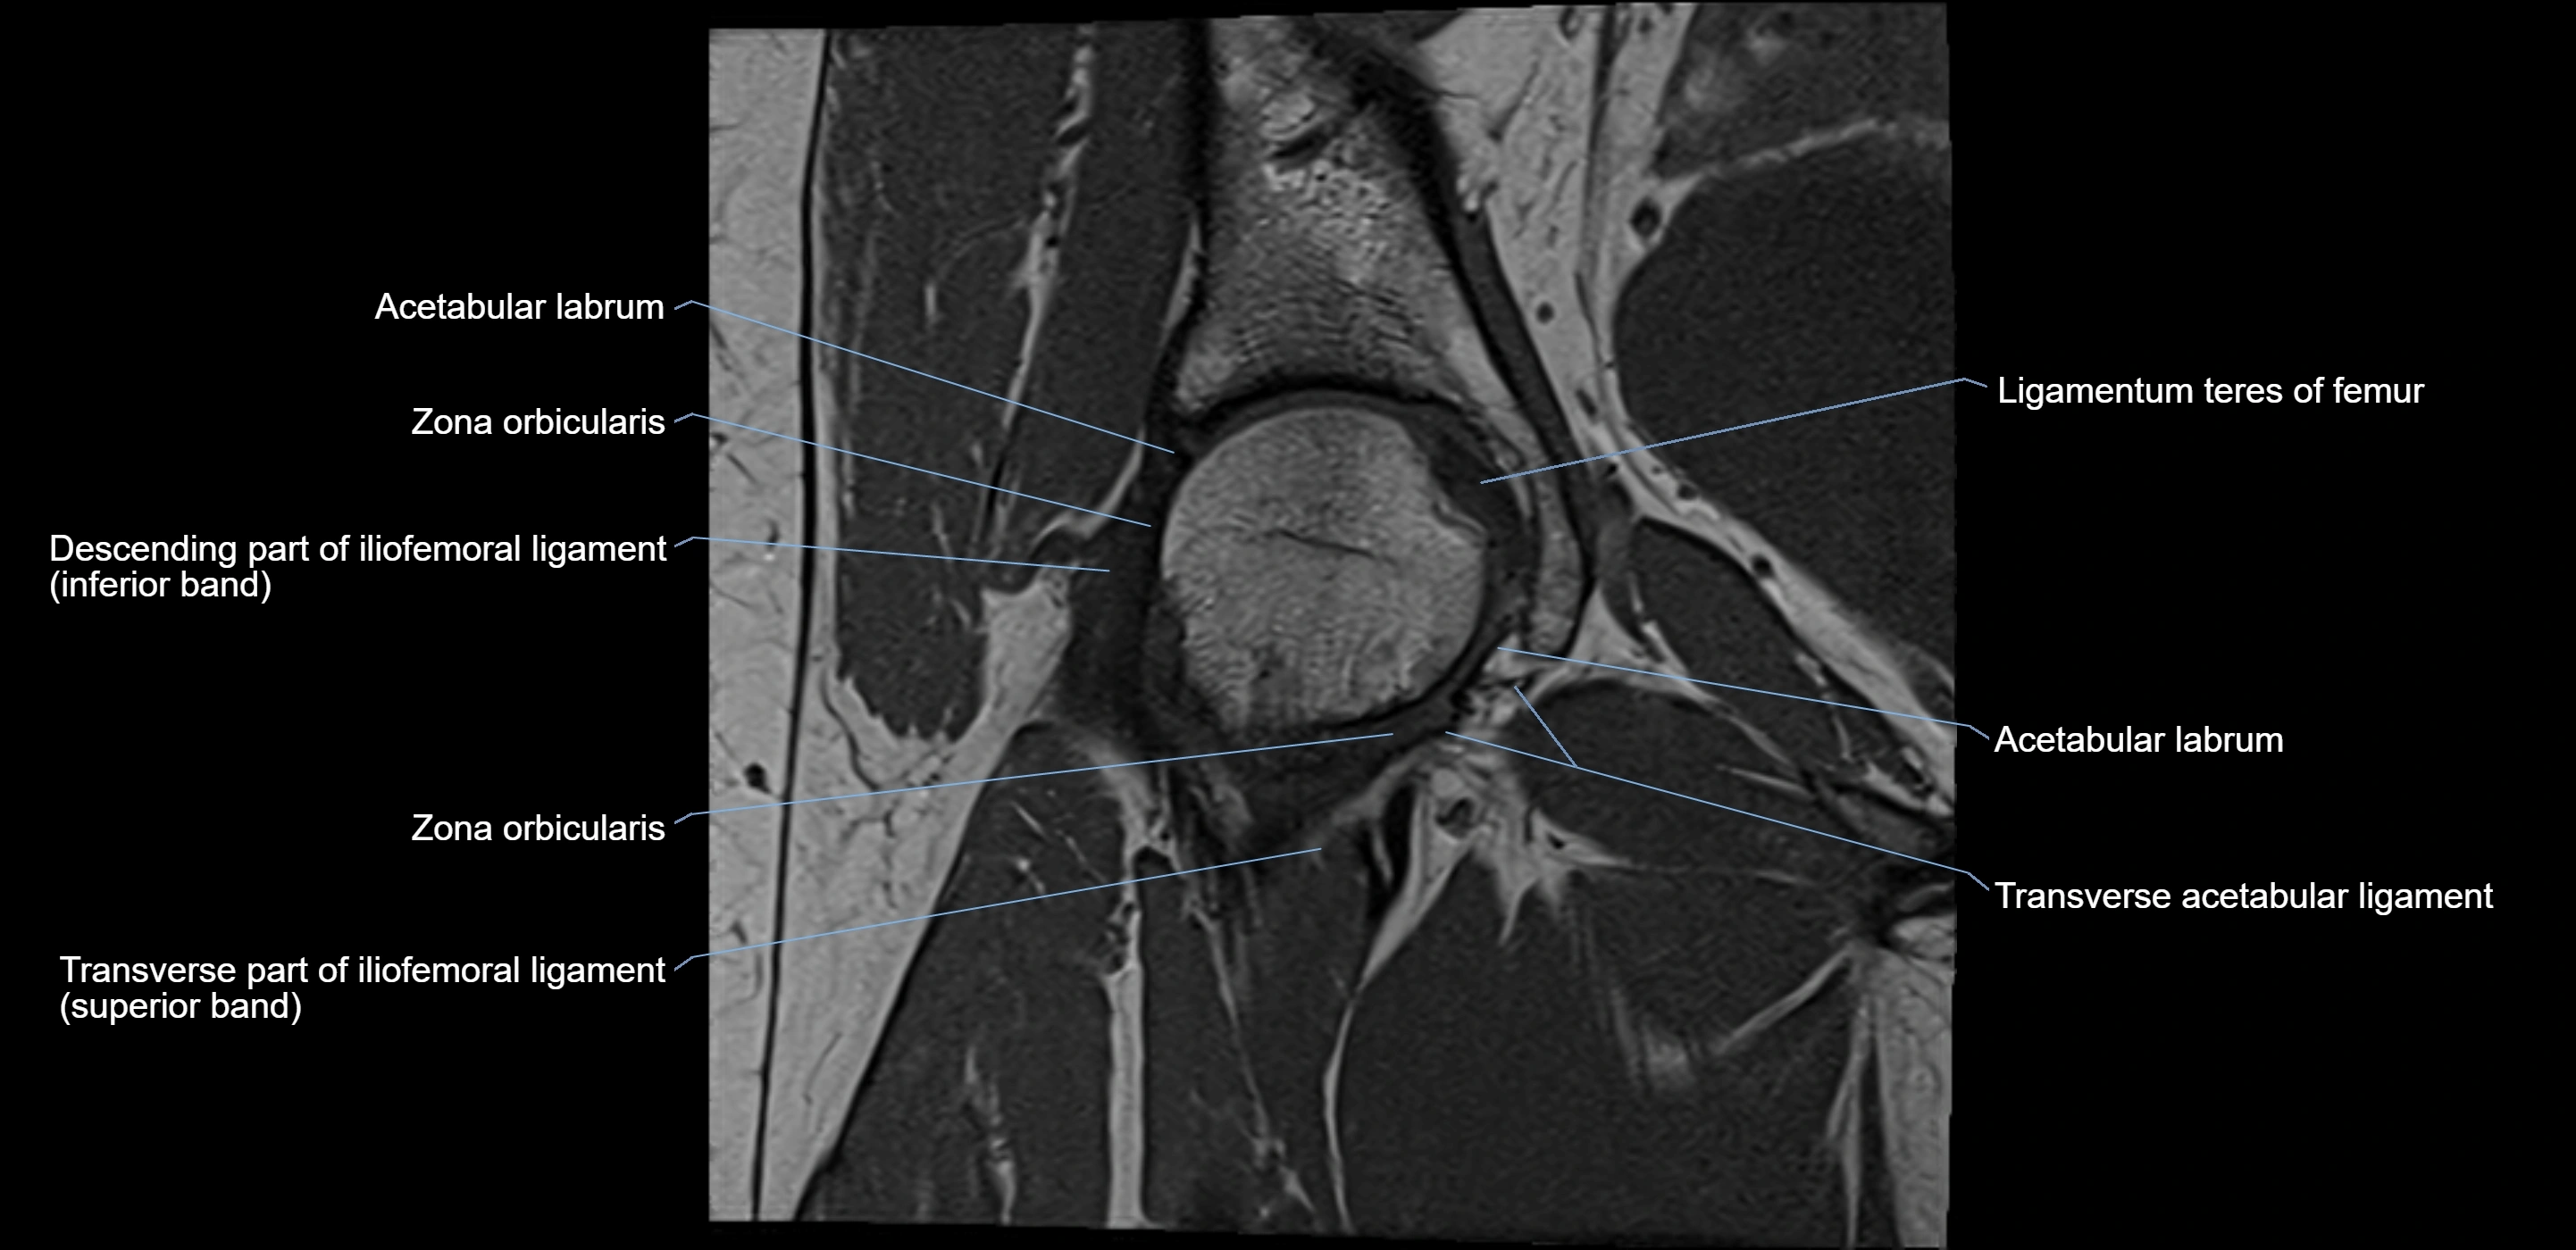

The acetabular labrum is a fibrocartilaginous ring that surrounds the rim of the acetabulum in the hip joint. It deepens the hip socket, increases joint stability, and maintains a suction seal that preserves negative intra-articular pressure. Structurally, the labrum transitions from hyaline cartilage of the acetabulum to dense fibrocartilage at its free edge.

It is triangular in cross-section, with its base attached to the acetabular rim and its apex projecting toward the femoral head. The labrum is most robust superiorly and anteriorly, where load bearing is greatest, and relatively thinner inferiorly.

Structure and Relations

• Superior and anterior labrum: thickest portions, stabilizing against anterior dislocation

• Inferior labrum: blends with the transverse acetabular ligament bridging the acetabular notch

MRI Appearance

T1-weighted images:

• Labrum: low signal intensity (dark)

• Surrounded by intermediate signal joint fluid (bright on arthrogram)

• Tears: linear or focal areas of intermediate-to-high signal interrupting labral continuity

T2-weighted images:

• Joint fluid: bright, making labral tears visible as fluid extending into or around labrum

• Degeneration: may show areas of increased signal within labrum